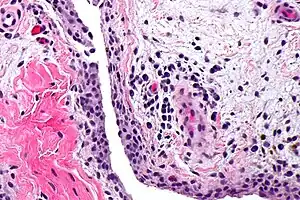

| Chronic synovitis | |

Synovitis is the medical term for inflammation of the synovial membrane. This membrane lines joints that possess cavities, known as synovial joints. The condition is usually painful, particularly when the joint is moved. The joint usually swells due to synovial fluid collection.

Synovitis may occur in association with arthritis as well as lupus, gout, and other conditions. Synovitis is more commonly found in rheumatoid arthritis than in other forms of arthritis, and can thus serve as a distinguishing factor, although it is also present in many joints affected with osteoarthritis.[1][2] In rheumatoid arthritis, the fibroblast-like synoviocytes, highly specialized mesenchymal cells found in the synovial membrane, play an active and prominent role in the synovitis.[3] Long term occurrence of synovitis can result in degeneration of the joint.